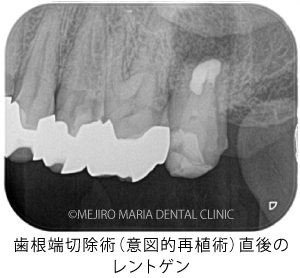

歯根端切除術(意図的再植術)から3週間後の経過観察で、瘻孔の消失が確認できました。また、術後3ヶ月経つと、根尖部付近に確認できていた根尖性歯周炎も小さくなりました。患者様も「噛んだときにも、違和感や痛みなどはない」ということで、予後は良好だと判断しました。今後は最終補綴処置を行う予定です。

今回の症例の患者様は、病変が大きいことから、かかりつけ医に抜歯を宣告されて、当院へ相談に来られました。当院の治療により、瘻孔(フィステル)は消失し、歯根端切除術(意図的再植術)3ヶ月後の経過観察では、明らかな病変の縮小が確認されました。